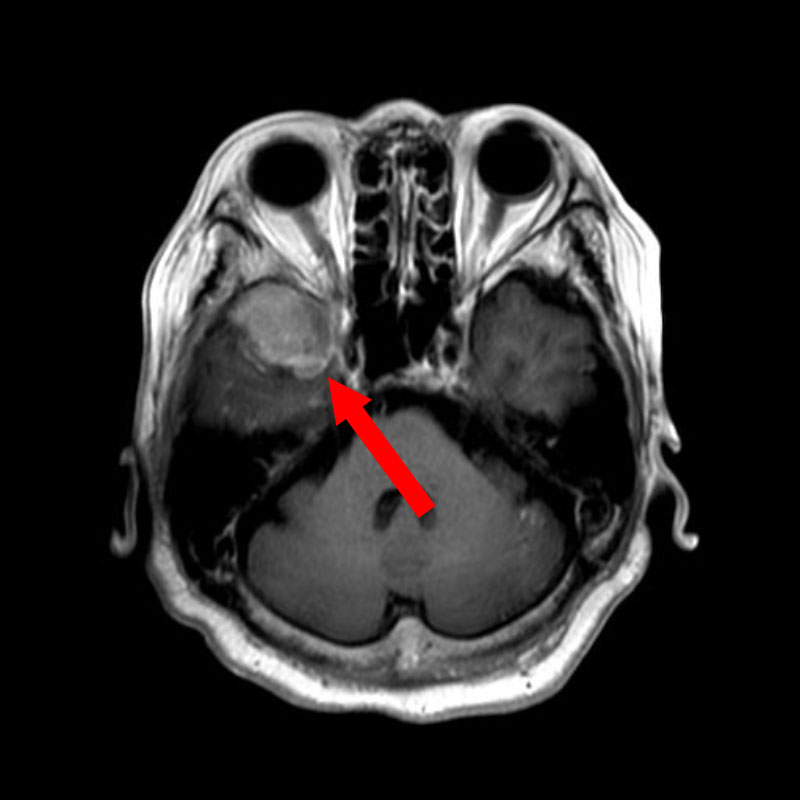

No.’25_103 手術前1

No.’25_103 手術前2